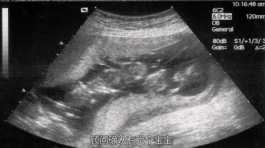

A:你好,阴道超声检查不需要憋尿,但需要排空膀胱。但一般无性史、阴道发育异常等特殊情况需要腹部超声检查充满膀胱,作为声窗,以便更清晰地显示盆腔情况。...